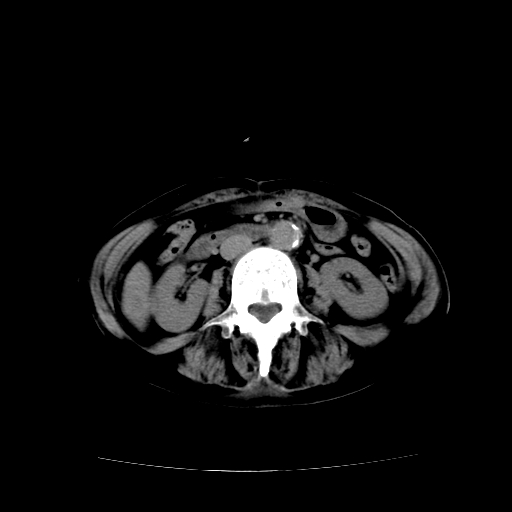

女70y乳腺ca(针吸活检)

多部位转移瘤的诊断可以肯定,我的疑问是:双肺对称高密度影及胸水是否为心衰肺水肿,病人体虚弱,不好意思图象传的乱![em9]

1)左侧乳腺癌并左侧腋窝及纵隔淋巴结转移,两肺淋巴道转移(癌性淋巴管炎),肝脏多发性转移。2)双侧胸腔积液。3)慢性胆囊炎。

癌性淋巴管炎,胸膜转移.肝内转移,纵隔及腋窝淋巴结转移

1)左侧乳腺癌并左侧腋窝及纵隔淋巴结转移,肝脏多发性转移。2)双侧胸腔积液伴双肺蝶翼样磨玻璃高密度影,双侧肺门血管影增粗(图像不全,肺门层面没纵隔窗),考虑心功能不全所致。3)慢性胆囊炎伴壁钙化。